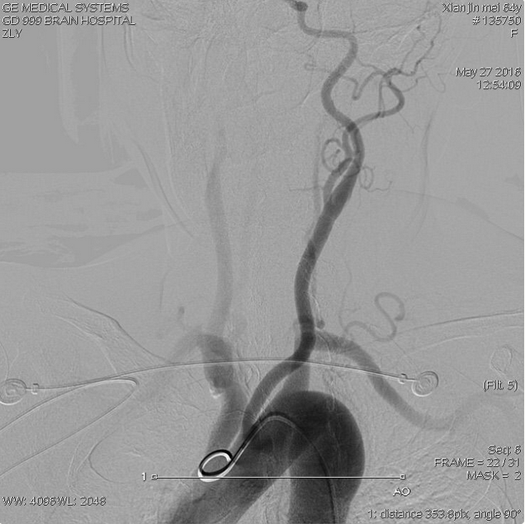

造影示:三型弓,升主动脉与主动脉弓连接处迂曲角度大

常规路径完成造影、栓塞难度大,选择经桡动脉路入,右侧锁骨下动脉造影

右椎动脉造影:右侧小脑后下动脉瘤,大小约2.7×3.0mm;瘤颈口与右侧小脑后下动脉开口关系密切